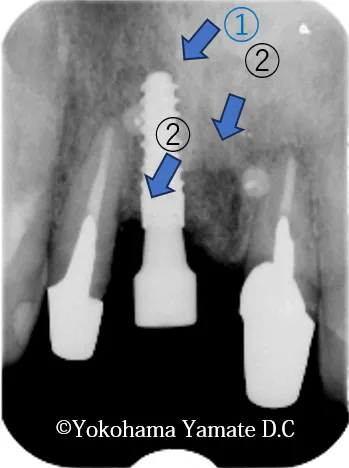

治療途中経過

2021年4月21日 外傷による欠損歯はインプラント埋入・ソーセージテクニックによる増骨手術①

2022年5月12日 パッチテクニック手術を加えての増骨②と歯肉の増生a

インプラント手術後1年6ヵ月

(2022年10月)